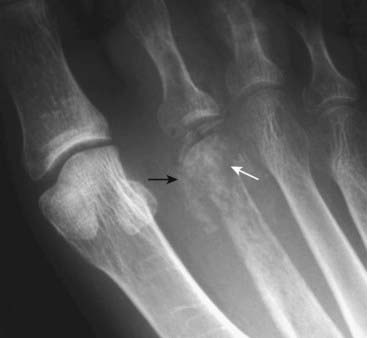

Figure 21-25 Acute osteomyelitis of 2nd metatarsal.

Close-up view of the 2nd toe in this 59-year-old female with diabetes shows the hallmarks of bone destruction (solid white arrow) and periosteal new bone formation (solid black arrow) in osteomyelitis.